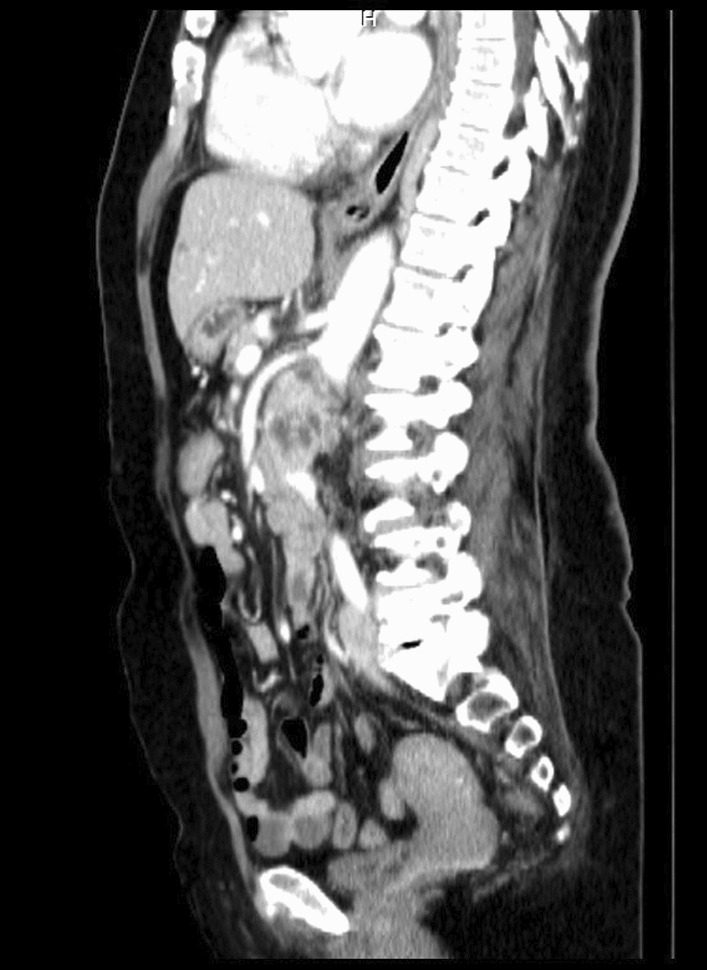

Fig. 2.

Preoperative computed tomography angiography, sagittal view

After a comprehensive assessment, which included urine analysis, complete blood count, electrolytes, renal and hepatic function tests, as well as ultrasonography and computed tomography, she was diagnosed with left kidney renal cell carcinoma involving the left renal vein and subhepatic inferior vena cava (Figs. 1, 2). All tests came back normal, except for microhematuria and slight hypoalbuminemia. A minor increase in C-reactive protein was also noted (Table 1).